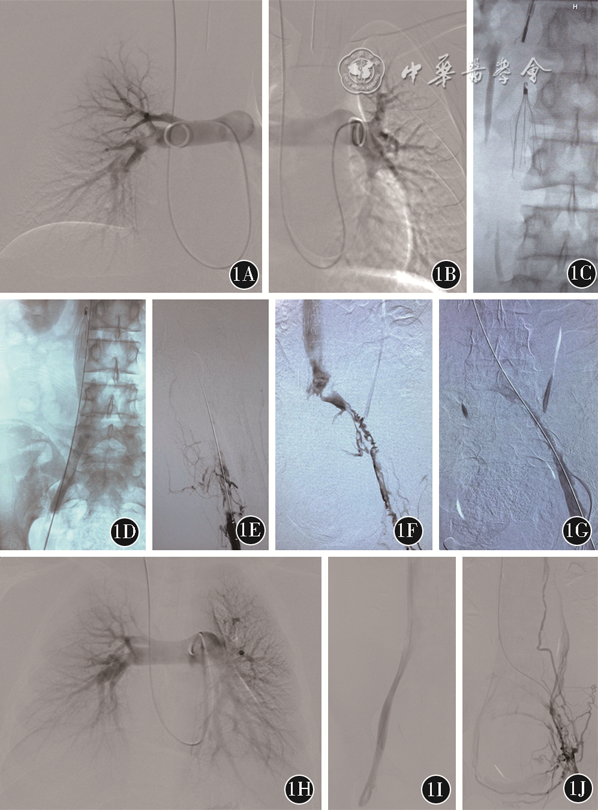

遂于2021年8月9日急诊行下腔静脉滤器置入+髂股静脉血栓清除术(图2)。经右侧股静脉入路于下腔静脉肾下段放置下腔静脉滤器;经左侧腘静脉入路,行左侧髂-股静脉AngioJet PMT,应用尿激酶20万U;术中见左侧股浅静脉血栓疏松,极易脱落至左侧髂静脉、下腔静脉滤器下方,术中指氧监测一过性下降至68%,5 min内自行缓解。术后予低分子肝素(8000 IU,每12 h 1次)皮下注射。于2021年8月16日出院。